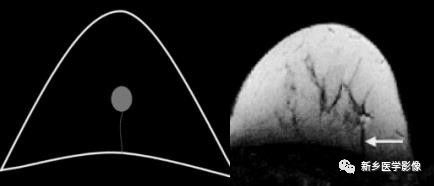

肺实变与肺不张的CT鉴别诊断